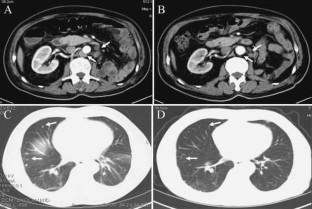

Fig. 2